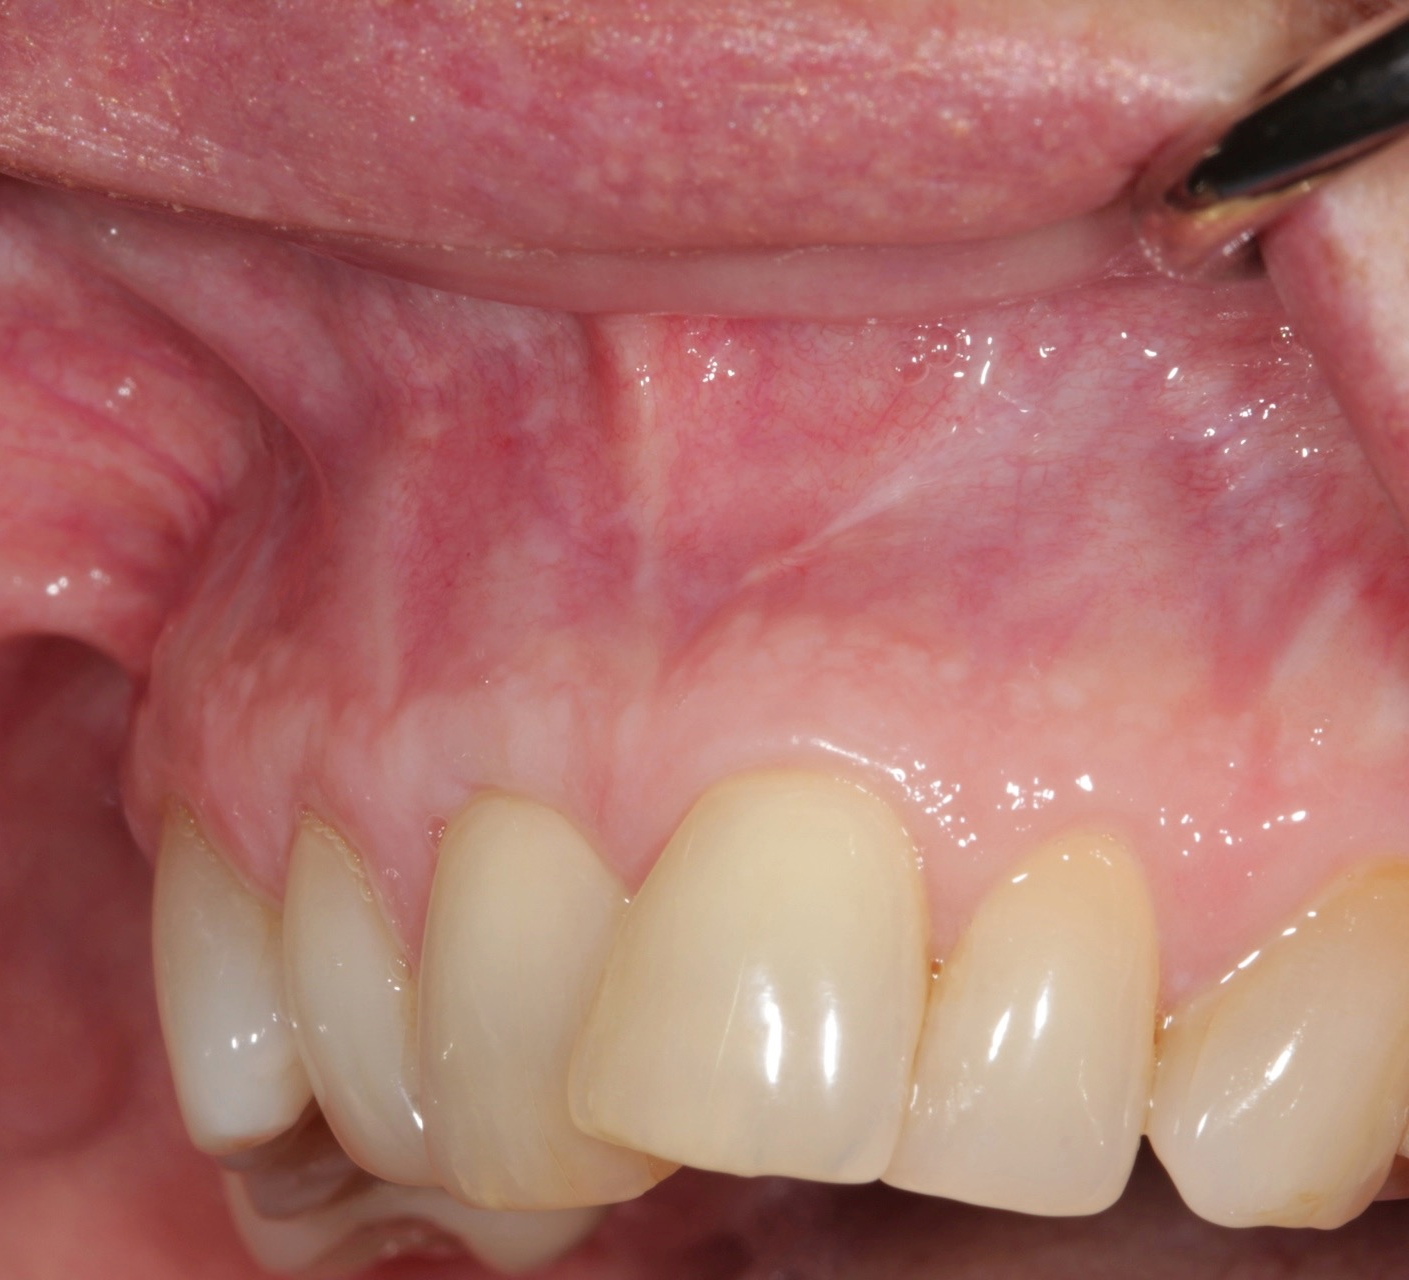

Fig 5. Preoperative. Class 2 Miller trauma-induced recession and associated tooth malposition.

Figure 5